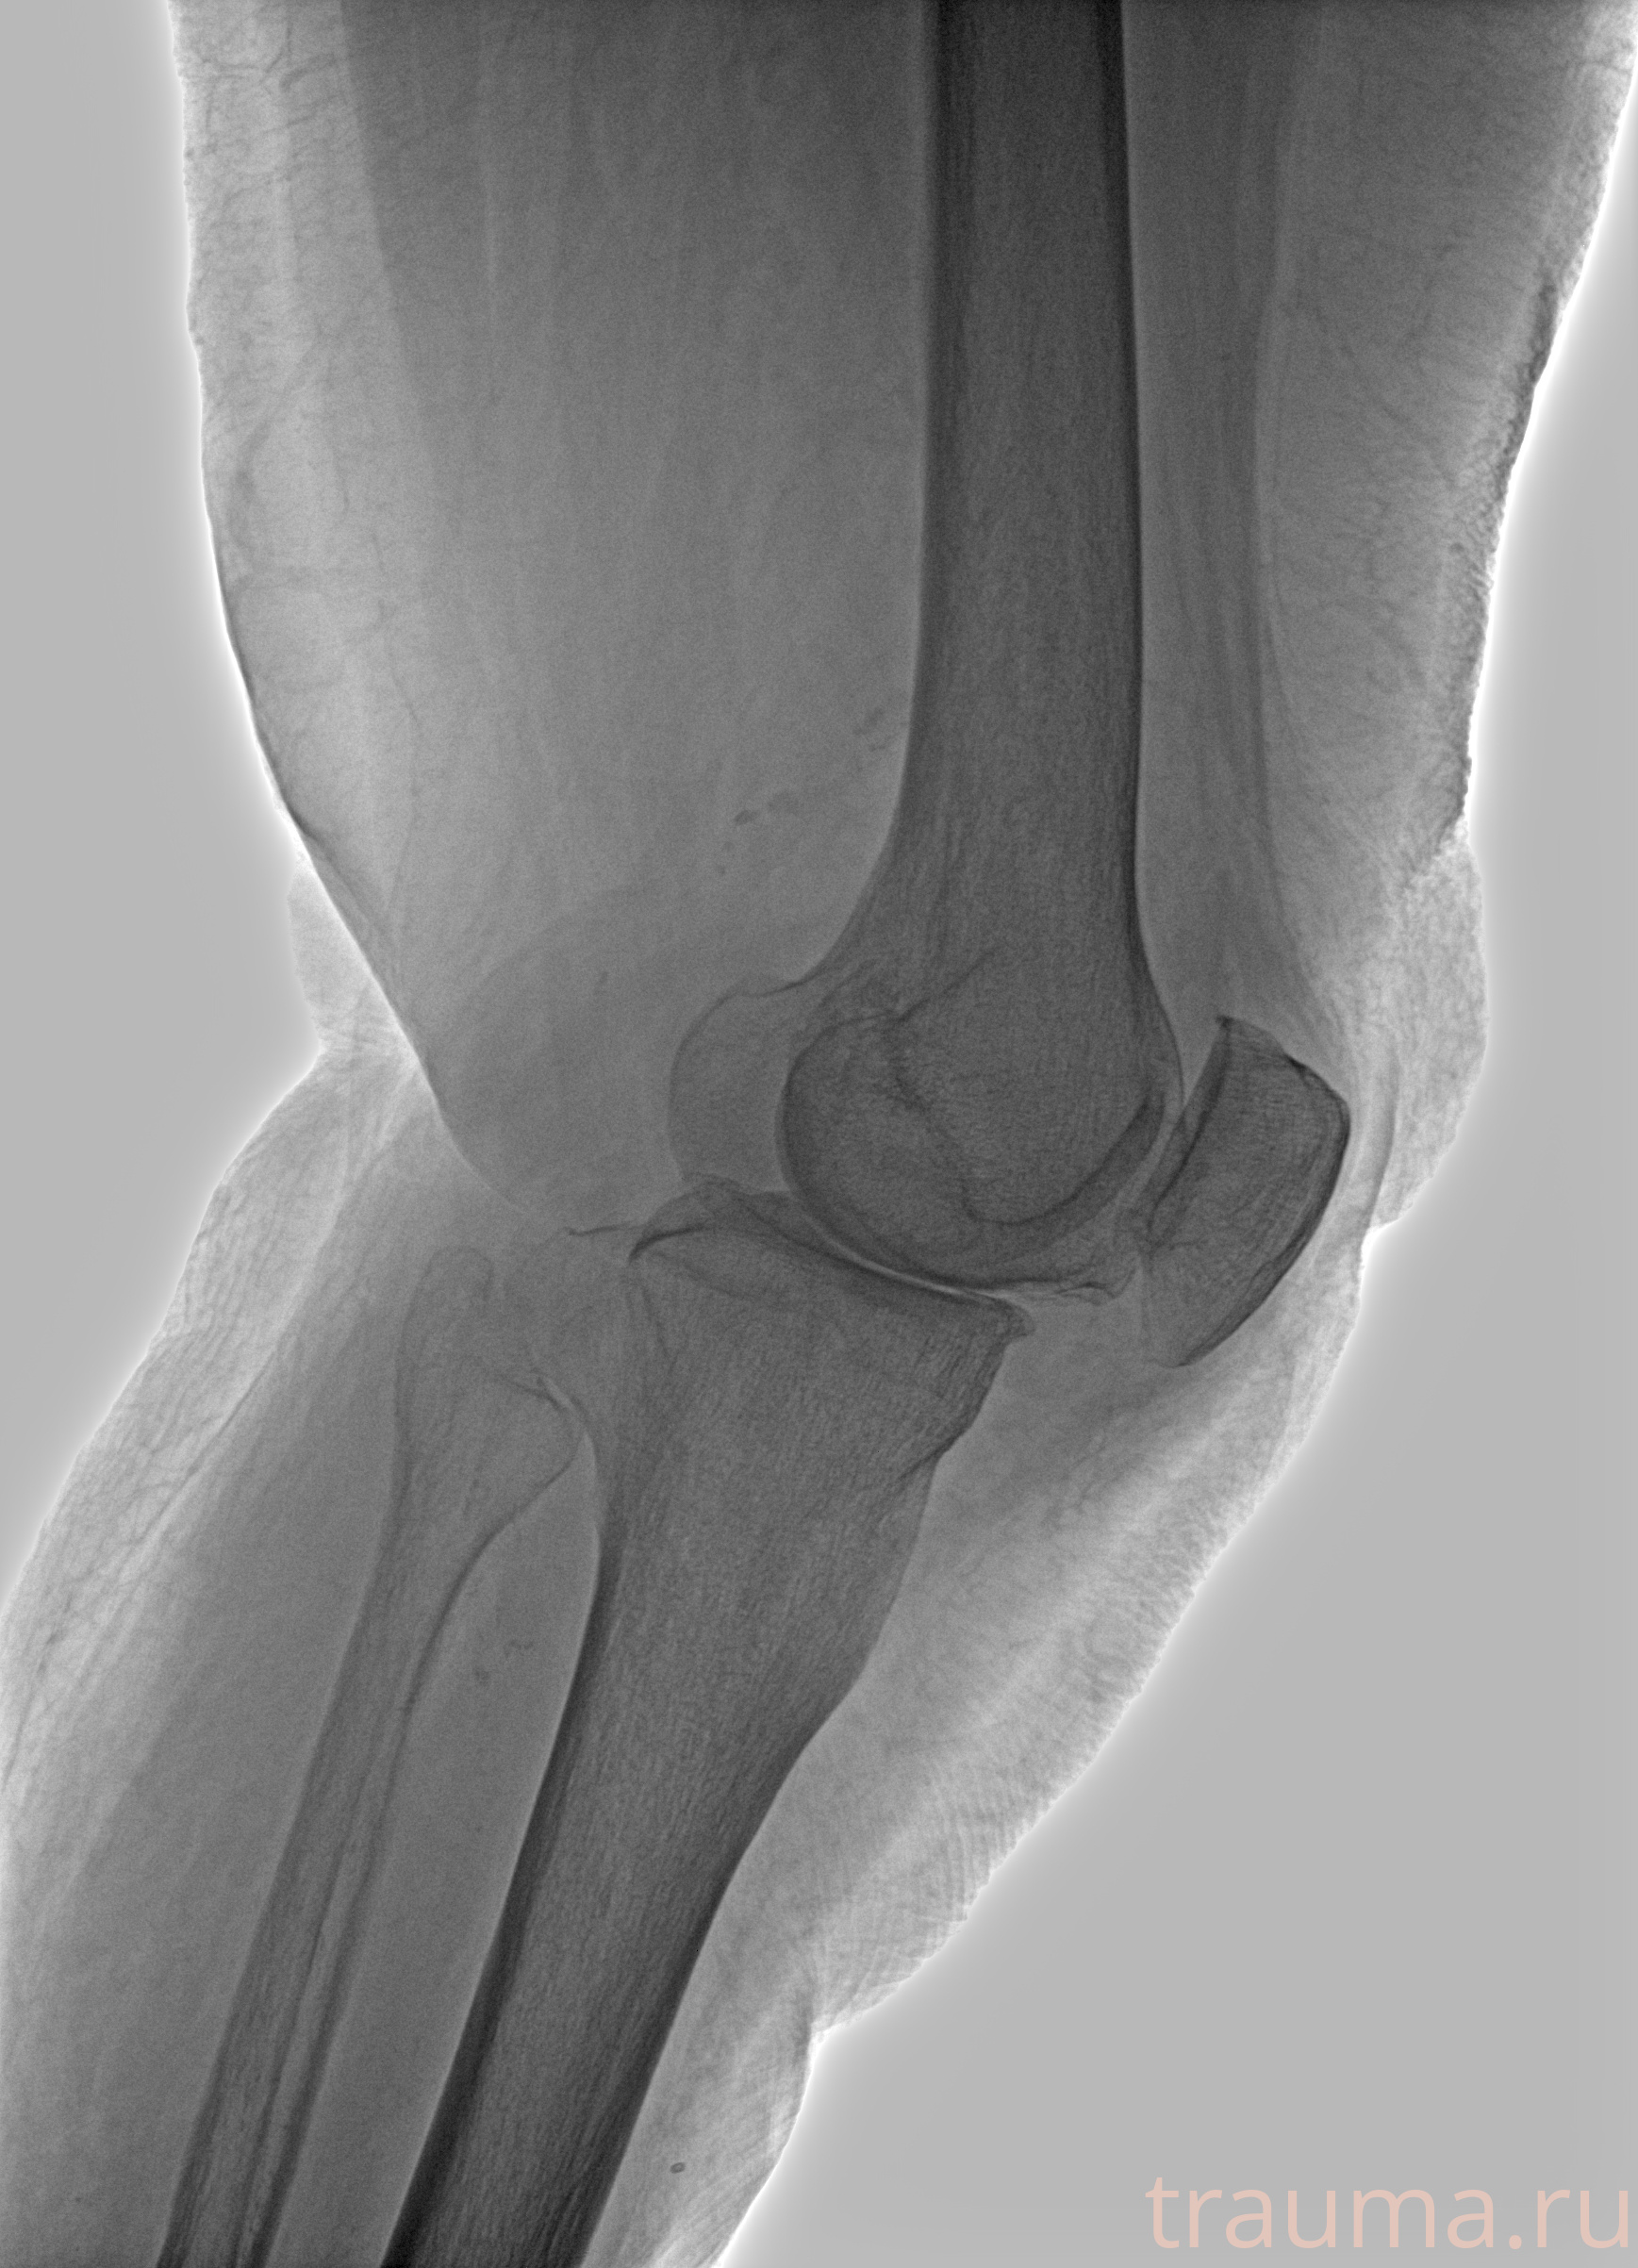

Правая

Рентгенограммы

Рентген на дому: по вашему адресу приезжает врач-рентгенолог, травматолог-ортопед с мобильным рентгеновским аппаратом, проводит диагностику травмы или заболевания, делает необходимые рентгенограммы, дает рекомендации по дальнейшему лечению. Получить качественные снимки в домашних условиях возможно благодаря уникальной методике, разработанной МосРентген Центром для института  Склифосовского